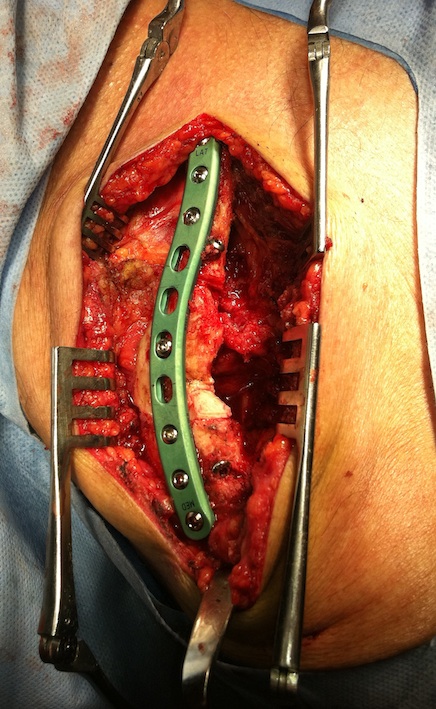

Technique

Vumedi clavicle ORIF with plate video

Lazy beach chair

- square drape / free drape

- LA with Adrenalin

Transverse incision in Langer’s line

- ? identify and protect supraclavicular nerves

- divide platysmus as a layer to repair later

- clean and reduce fracture

- application contoured locking plate

- need 6 cortices each side